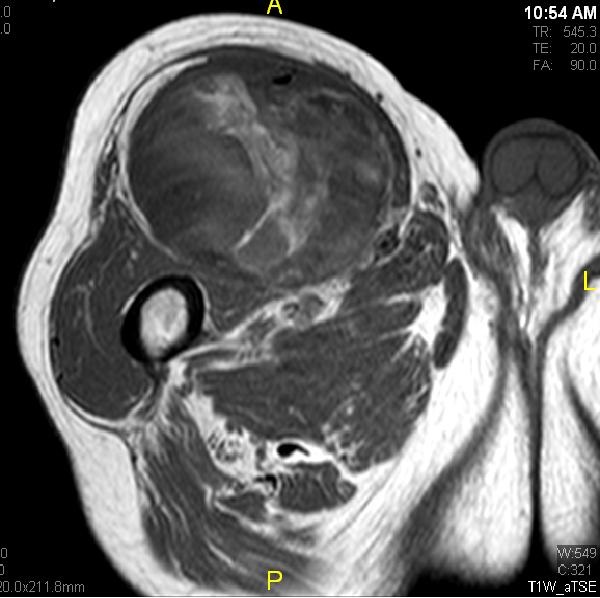

Fig. 7 & 8 Magnetic Resonance Image shows a large heterogeneous mass in the right thigh with low intensity signal on Axial (Fig. 7) and Coronal (Fig. 8) T1-weighted images admixed with high signal areas. The high signal areas represent low grade fatty tissue and low signal the dedifferentiated areas. Higher intensity signal is visible compatible with hemorrhage or necrotic tissue.

Fig. 10 Axial T2 weighted MR image demonstrates a large well encapsulated heterogeneous mass with multiple thick internal trabeculations located in the anterior compartment of the thigh.